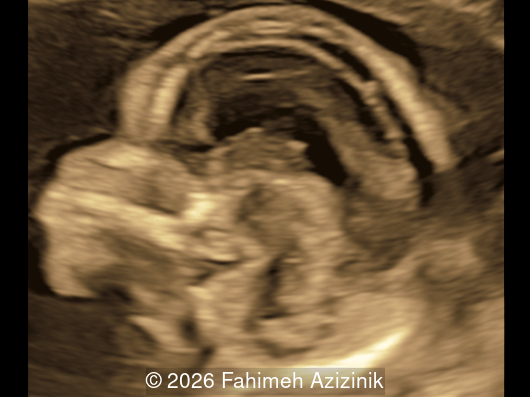

Image 1

Image 3

• Complex syndactyly of the hands and feet. Complex hand brachysyndactyly with “mitten-like” appearance due to bony fusion of the fingers

• Bicoronal craniosynostosis

• Hypertelorism

• Frontal bossing

Bicoronal synostosis is the characteristic cranial hallmark of Apert syndrome, detectable sonographically from 18 weeks. Its most recognizable manifestation is turribrachycephaly, defined by an elevated cephalic index (typically >85–90%) and a tall cranial vault with marked frontal bossing [19]. On prenatal ultrasound, the face in Apert syndrome shows midface hypoplasia with a depressed nasal bridge, proptosis, hypertelorism, and frontal bossing. The extremities demonstrate syndactyly of both bone and soft tissue of the hands and feet with partial-to-complete fusion often involving second, third, and fourth digits, known as “mitten hands” and “socked feet”. In severe cases, all digits are fused, with the presence of a single nail known as “synonychia” [20]. Other ultrasound findings include mild ventriculomegaly, agenesis of the corpus callosum, deficient or absent septum pellucidum, and fusion of the cervical vertebrae at the level of C5-C6 [21]. Cardiovascular (atrial and ventricular septal defect) and genitourinary anomalies (hydronephrosis, and cryptorchidia) are present in 10% of patients [22]. Increased nuchal translucency in the first trimester [23], widely open metopic suture [24], and polyhydramnios [25] have also been reported. Three-dimensional (3D) ultrasound facilitates assessment of surface abnormalities of the face and extremities, and magnetic resonance imaging (MRI) can be used to evaluate associated intracranial conditions [26].